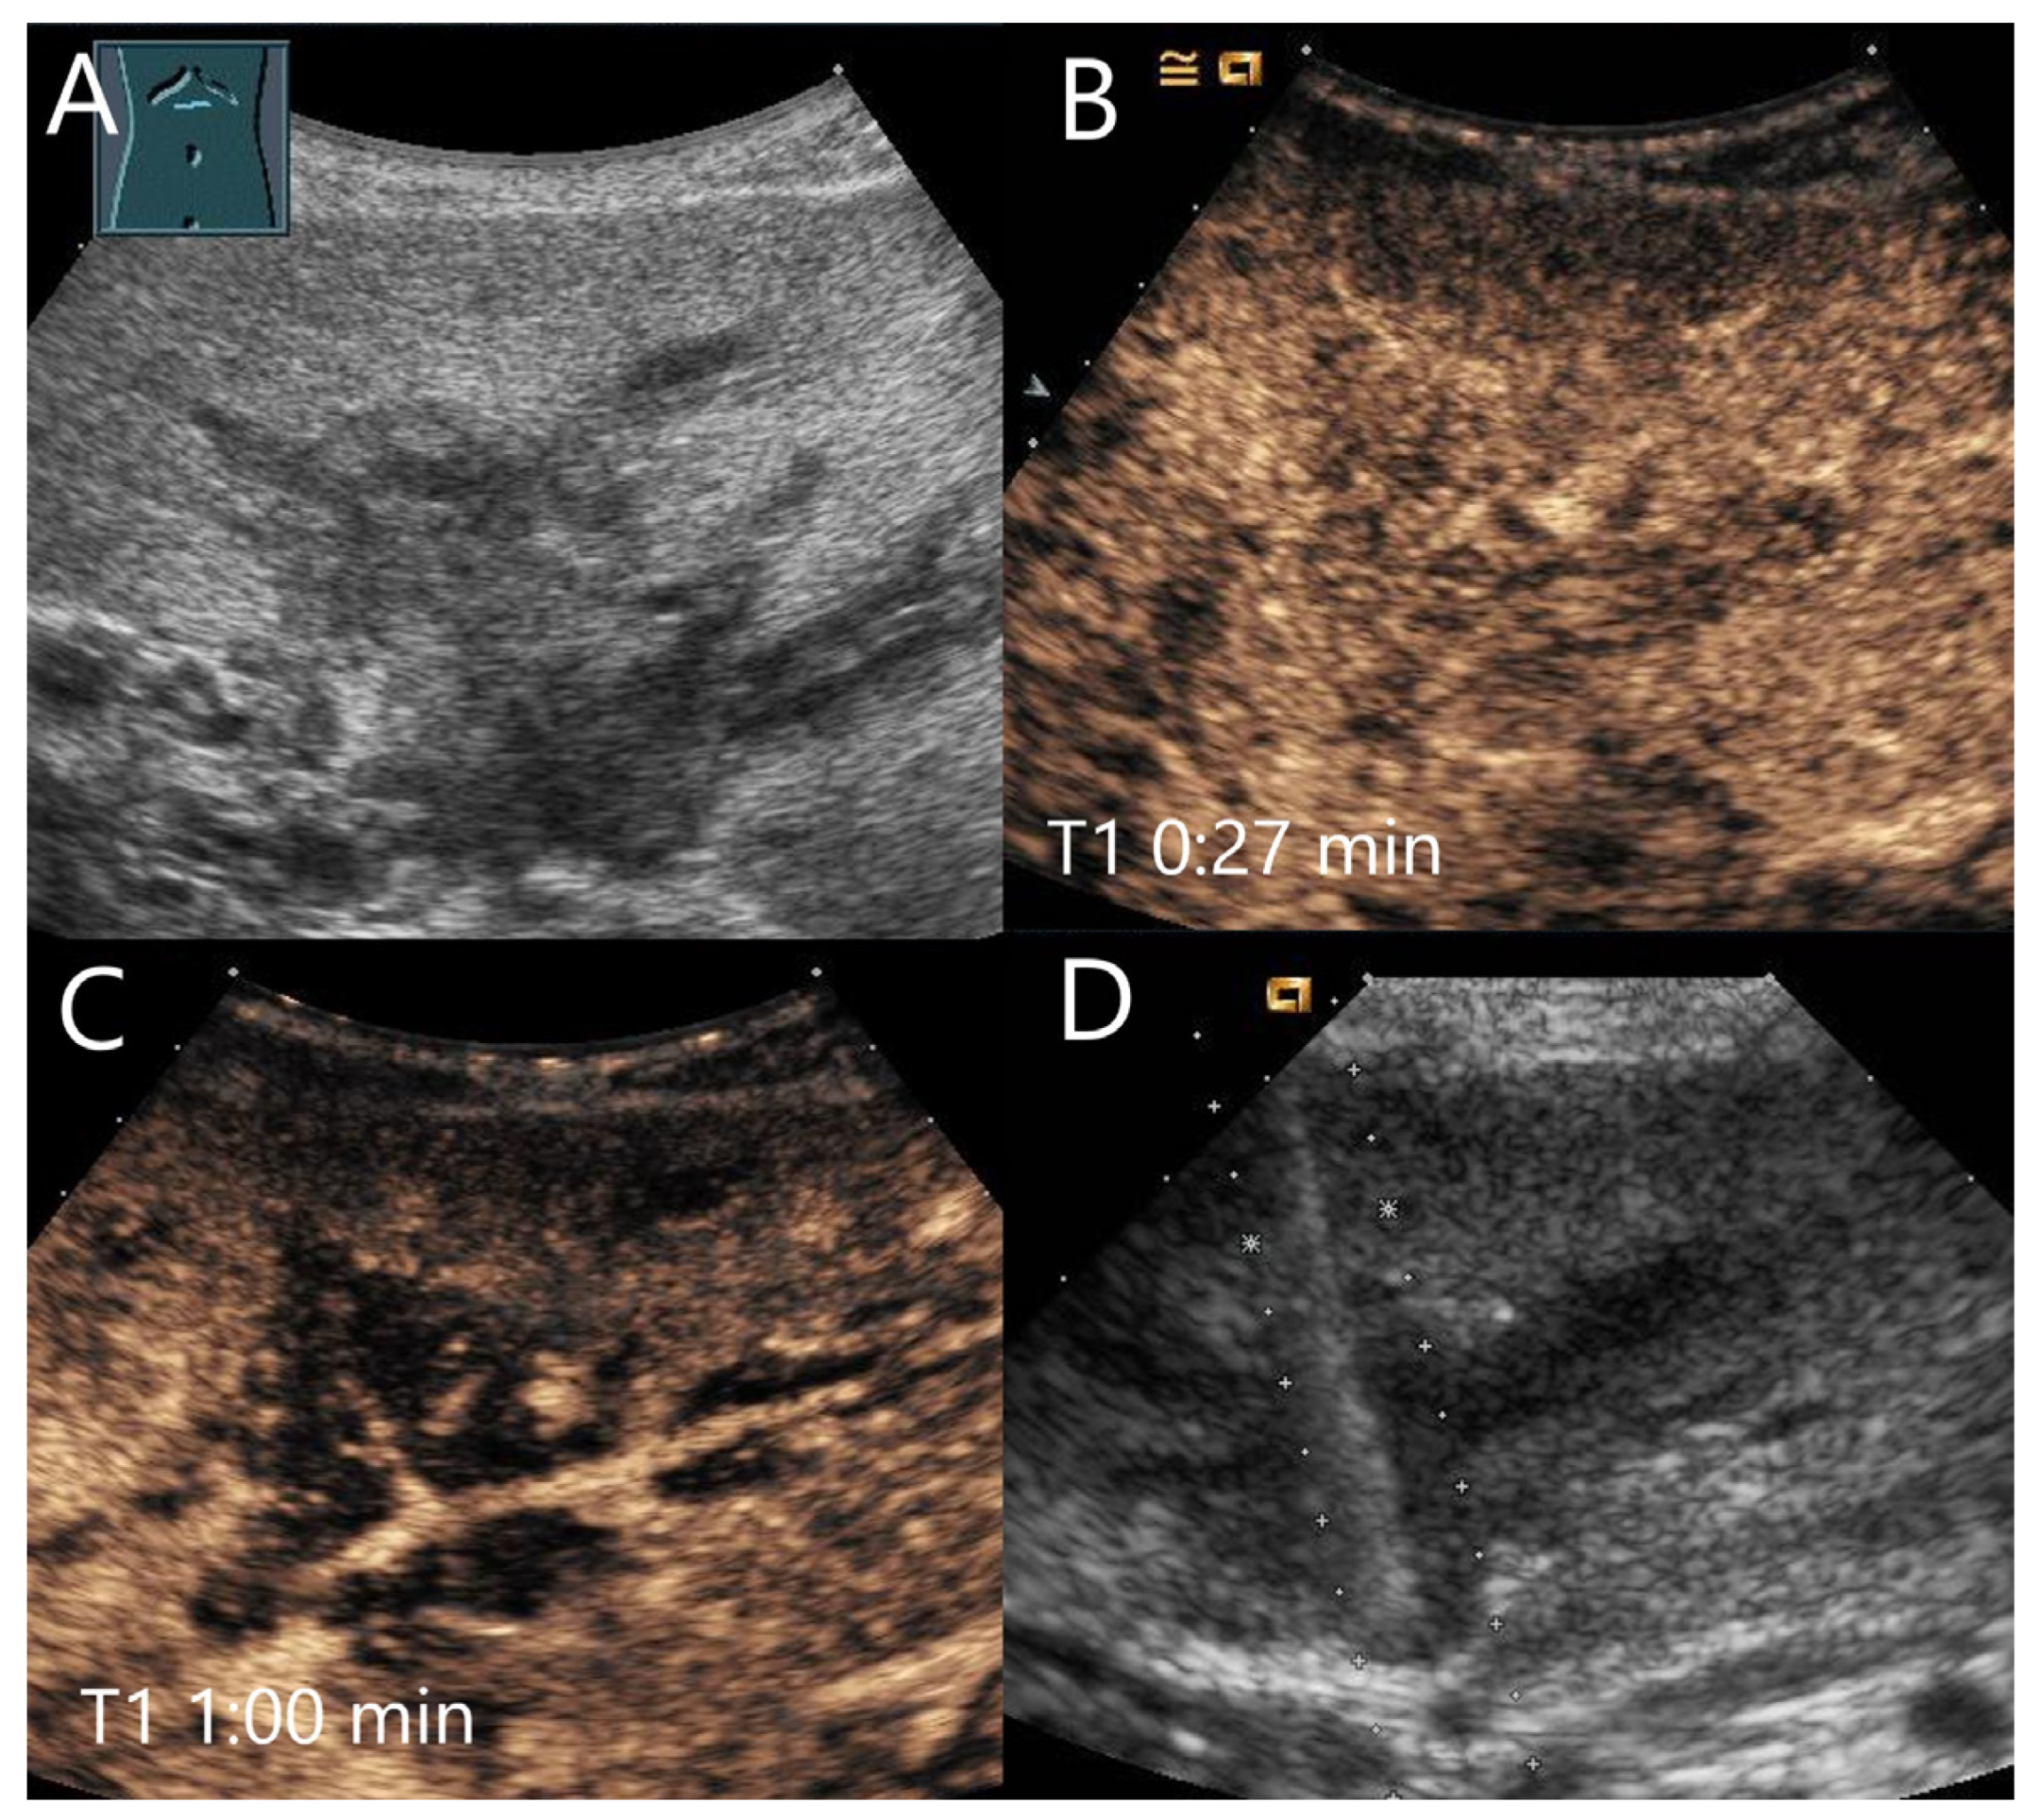

Figure 16.

IgG4-associated inflammatory pseudotumor. In a patient with elevated liver enzymes and alcohol abuse, B-mode US showed steatosis hepatis and a 55 × 20 mm irregular oval hypoechoic lesion (A). The central tubular structure was without flow evidence on CDI, and we interpreted this as a small bile duct branch. On CEUS, the lesion (arrows) was homogeneously hyperenhanced in the AP (B). In the PVP, a mild hypoenhancement developed (C), which became more pronounced in the LP (D).